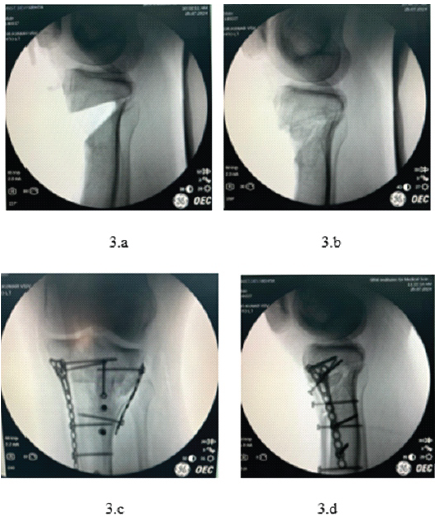

Figure 3: Intraoperative fluoroscopic images illustrating osteotomy and fixation stages. (a) Lateral view after completion of biplanar tibial tuberosity osteotomy, before graft placement and fixation; (b) Anteroposterior view after osteotomy, showing gap created for graft insertion; (c) Anteroposterior view following final implant fixation with tricortical graft in place; (d) Lateral view following dual-pillar plate fixation and tibial tuberosity screw placement.

Fig. 3 shows intraoperative fluoroscopic images demonstrating the osteotomy site (Fig. 3a and b) and the subsequent fixation with a locking plate and screws after deformity correction (Fig. 3c and d). These images illustrate the stepwise execution of the osteotomy and stabilization.